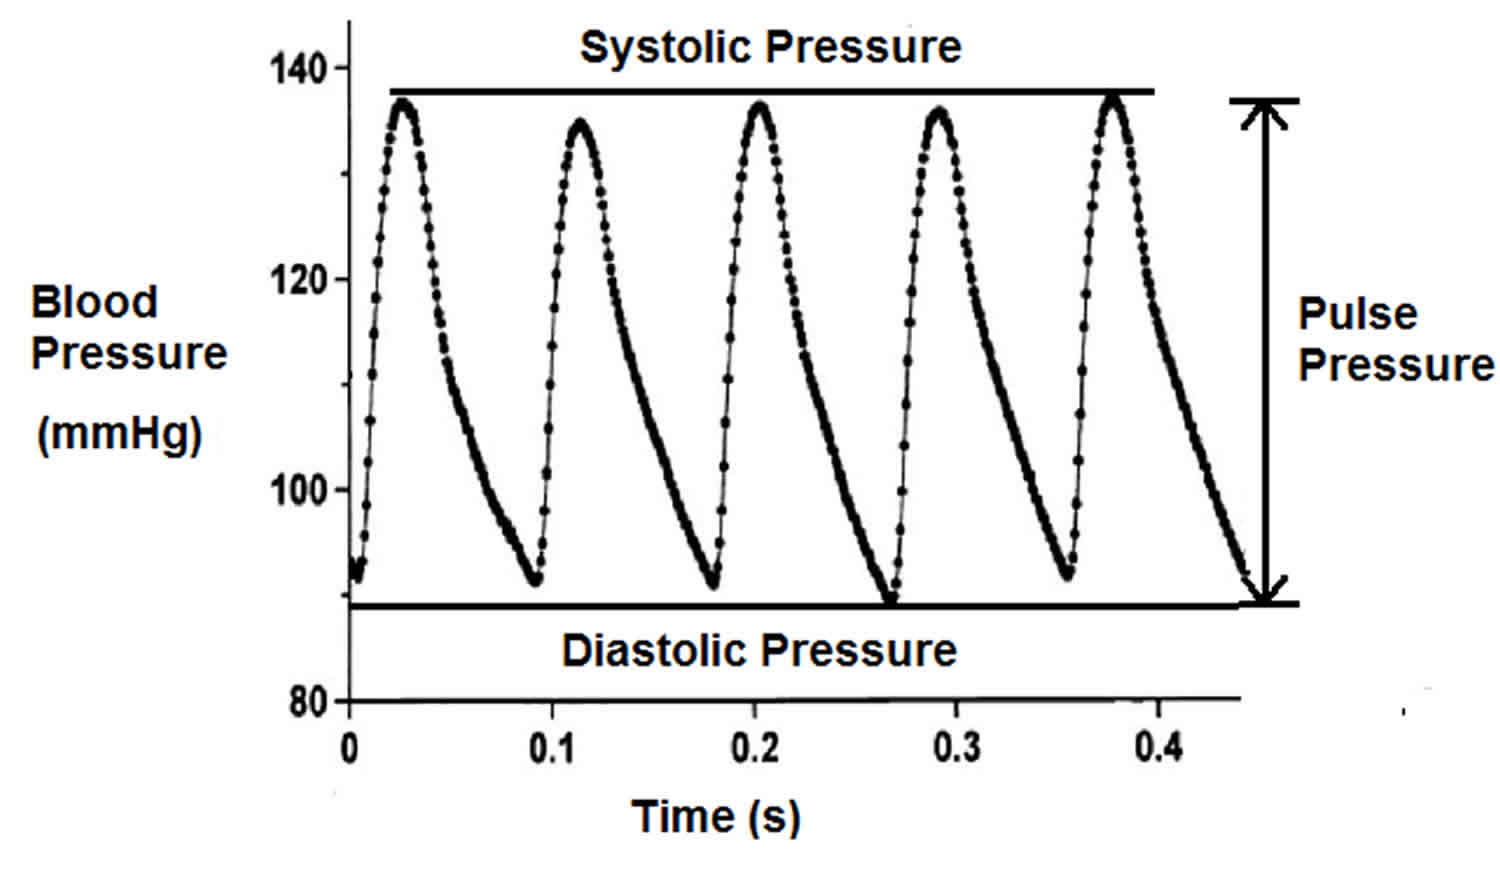

Pulse Pressure Virtgz

https://healthjade.net/wp-content/uploads/2020/01/pulse-pressure.jpg

Orthostatic Hypertension Symptoms Causes Diagnosis And Treatment